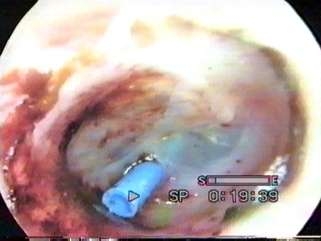

Son yıllarda birçok çocuğa kulak tüpü takıldığını duymuşsunuzdur; ancak cerrahi tedavi, kulakta sıvı birikimi durumunda ilk tercih edilen tedavi yöntemi değildir. İlk aşamada ilaç tedavisi yapılır. Eğer kulaktaki sıvı birikimi bu tedavilere rağmen devam ederse doktorunuz orta kulaktaki sıvıyı uzaklaştırmak için cerrahi tedavi, yani tüp takılmasını önerebilir. Kulak tüpü ameliyatında genel anestezi verilerek hasta 15- 30 dakika uyutulur. Her bir deri kesisi yapılmadan kulak tüpü kulak kanalından yerleştirilir. Burada önemli olan bir faktörde kulak tüpünün nasıl olacağidır.Genellikle kulak tüpü seçerken kaliteli tüpler tercih edilmelidir. Normalde kukta bu tüplerin bir yıl kalması arzulanır.Bu bir yıllık süreç kulaktaki sıvı sorununun genellikle çözümü için yeterli bir süredir.Fakat diğer bir unsurda tüp kulağa yerleştirildikten sonra kulak bunu yabancı bir cizim gibi algılayarak atmaya çalışacaktır. Bu nedenle tüpün kaliteli olması önemlidir. Ne kadar az reaksiyon oluşturursa atımı ve kulakta kalması istenen sürede olacaktır. Bu nedenle kaliteli altın tüp veya kaliteli floroplastik maddesi olan tüpler tercih edilmelidir. Avrupa veya Amerikan menşeyli tüpler tercih edilmelidir. Genellikle arzulanan süre bir yıl kalması iken tüpler 6. aydan sonra atım sürecine girebilirler. Atım sürecinde tüp yerleştiği noktadan kurtularak dış kulak yoluna düşer. Bu sırada zar tamamne kapnmış ve iyileşmiş duruma ulaşır. Bazende yastığa düşer. Bir yıl sonunda hala zar üzerinde bulunuyorsa çıkartılmalıdır.Bu işlem sırasında da genel anestezi gerekli olmaz. Basitçe muayene koltuğunda özel bir aletle çıkartılır. Tüm bu işlemlere rağmen kulakta sıvı toplanması meydana gelebilir. Genllikle grip, sinüzit veya burunda oluşan iltihaplar neticesinde görülebilir.

Basit antibiyotik ve bazı ilaçlarla iyleşme kolayca sağlanır. Tüm bunlara rağmen iyleşme olmuyorsa tekrar sıvı oluşumu varsa bu duruma '' reküren seröz otit'' adı verilir. Bu gibi durumlarda uzun süre kalacak ''T'' tüp adı verilen bir tüp çeşidi zara yerleştirilir. Östaki kanalı balon dilatasyon yöntemiylede rahatlatılabileceği akılda tutulmalıdırç Bazen bu durun öztaki kanalının daralmasından kaynaklanıyorsa östaki kanalı balon ile diletasyonu T tüpe gerek kalmadan sorunu çözebilir. Op.Dr.A.Ahmet Şirin

AŞAĞIDA KULAK ZARINA UYGULANAN TÜP ÇEŞİTLERİ: ( Sırası ile Altın tüp, Floroplastik tüp, T silikon tüp )